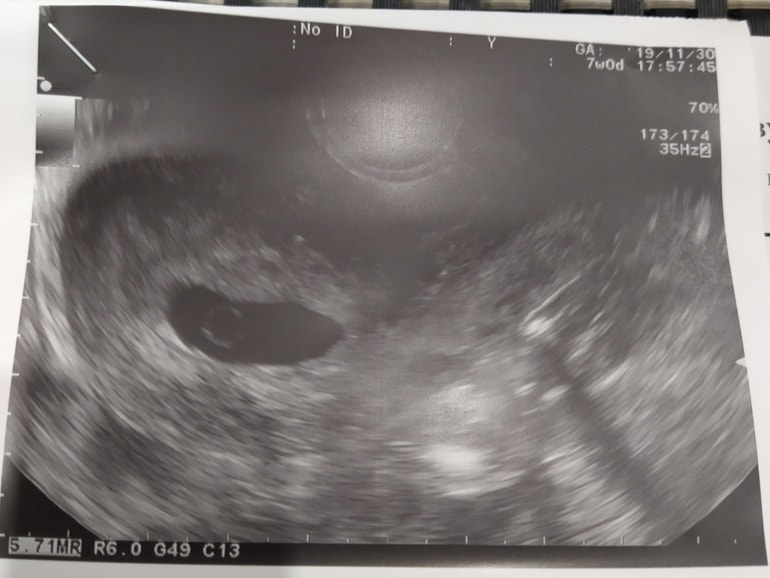

28.06 была на узи, поставили заключение замершая беременность в сроке 6-7 недель , анэмриония. Плодной яйцо 21,4 мм. Сказала идти на чистку.

Но после осмотра смотрю на фото узи и вижу такую картину. Как можно такое не увидеть?Я же не одна вижу? Как увидела это кружочек чуть успокоилась🥹 и начала писать другим врачам. Все написали что «надо на повторное узи, а на чистку не ходите ни в коем случай. Ещё рано так твердить и тем более отправлять на чистку»

У меня была анэмбриония с жм,пя росло хорошо,жм был,но не спас, эмбрион не появился по сроку и потом ждала почти до 8 недель и овуляция отслежена была и была на 14 д.ц

Динамика по УЗИ

5,1 акушерских пя 7 мм

6,5 акушерских пя 20,жм 5, эмбриона нет,под вопросом анэмбриония

7,0 акушерских пя 22,6,жм 5,5 анэмбриония

7,3 акушерских пя 26,жм 6,4 анэмбриония

7,5 медикаментозный аборт и на третий цикл новая здоровая беременность наступила и динамика такая

5,1 акушерских пя 8 мм,жм 1,6

6,3 акушерских пя 19,ктр 5,4 и ЧСС 146 уд/мин

8,0 акушерских пя 28,ктр 18 и ЧСС 180

Как потом мне говорила врач у меня не чистая анэмбриония была,когда вообще эмбрион не зарождается,а замершая на очень раннем сроке, поэтому жм и был,а эмбрион замер до того как его можно увидеть было по УЗИ, поэтому и анэмбриония по УЗИ